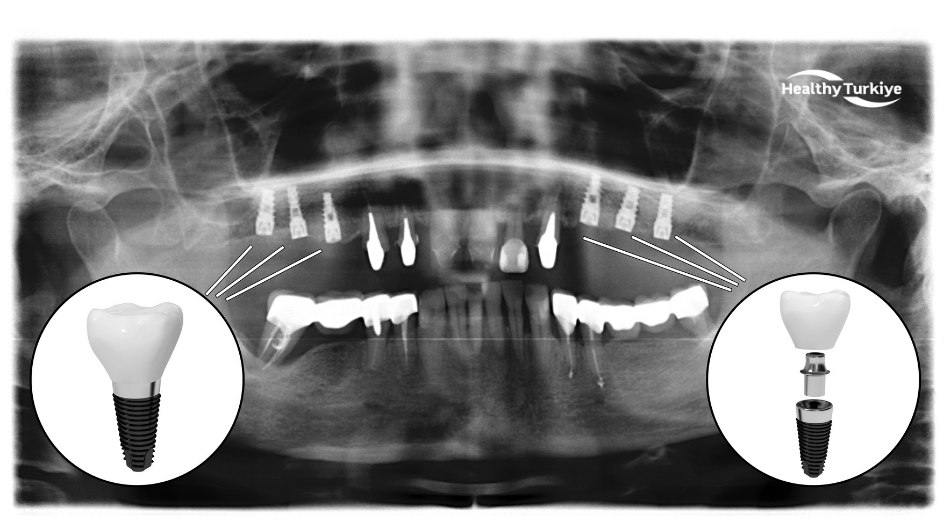

Unlike traditional solutions, full mouth implants Turkey provide a fixed, long-term alternative that closely mimics natural teeth in both function and appearance. Titanium dental implants are surgically placed into the jawbone, where they integrate through a biological process called osseointegration. These implants act as artificial tooth roots and support a full set of prosthetic teeth.

Full mouth dental implants Turkey, also known as full-arch implants or “teeth in a day” in some cases, are a permanent solution for people who have lost most or all of their teeth. Instead of replacing each missing tooth with an individual implant, a few strategically placed implants can support a full arch of prosthetic teeth. Typically, 4 to 6 implants per jaw are used to anchor a complete bridge of 10–14 teeth, fully restoring the upper or lower set. These implants are titanium posts surgically placed into the jawbone; they act as artificial tooth roots onto which a fixed prosthesis (the full set of replacement teeth) is attached. Over several months, the implants fuse with the bone in a natural process called osseointegration, creating a strong, stable foundation so the new teeth function just like real ones.